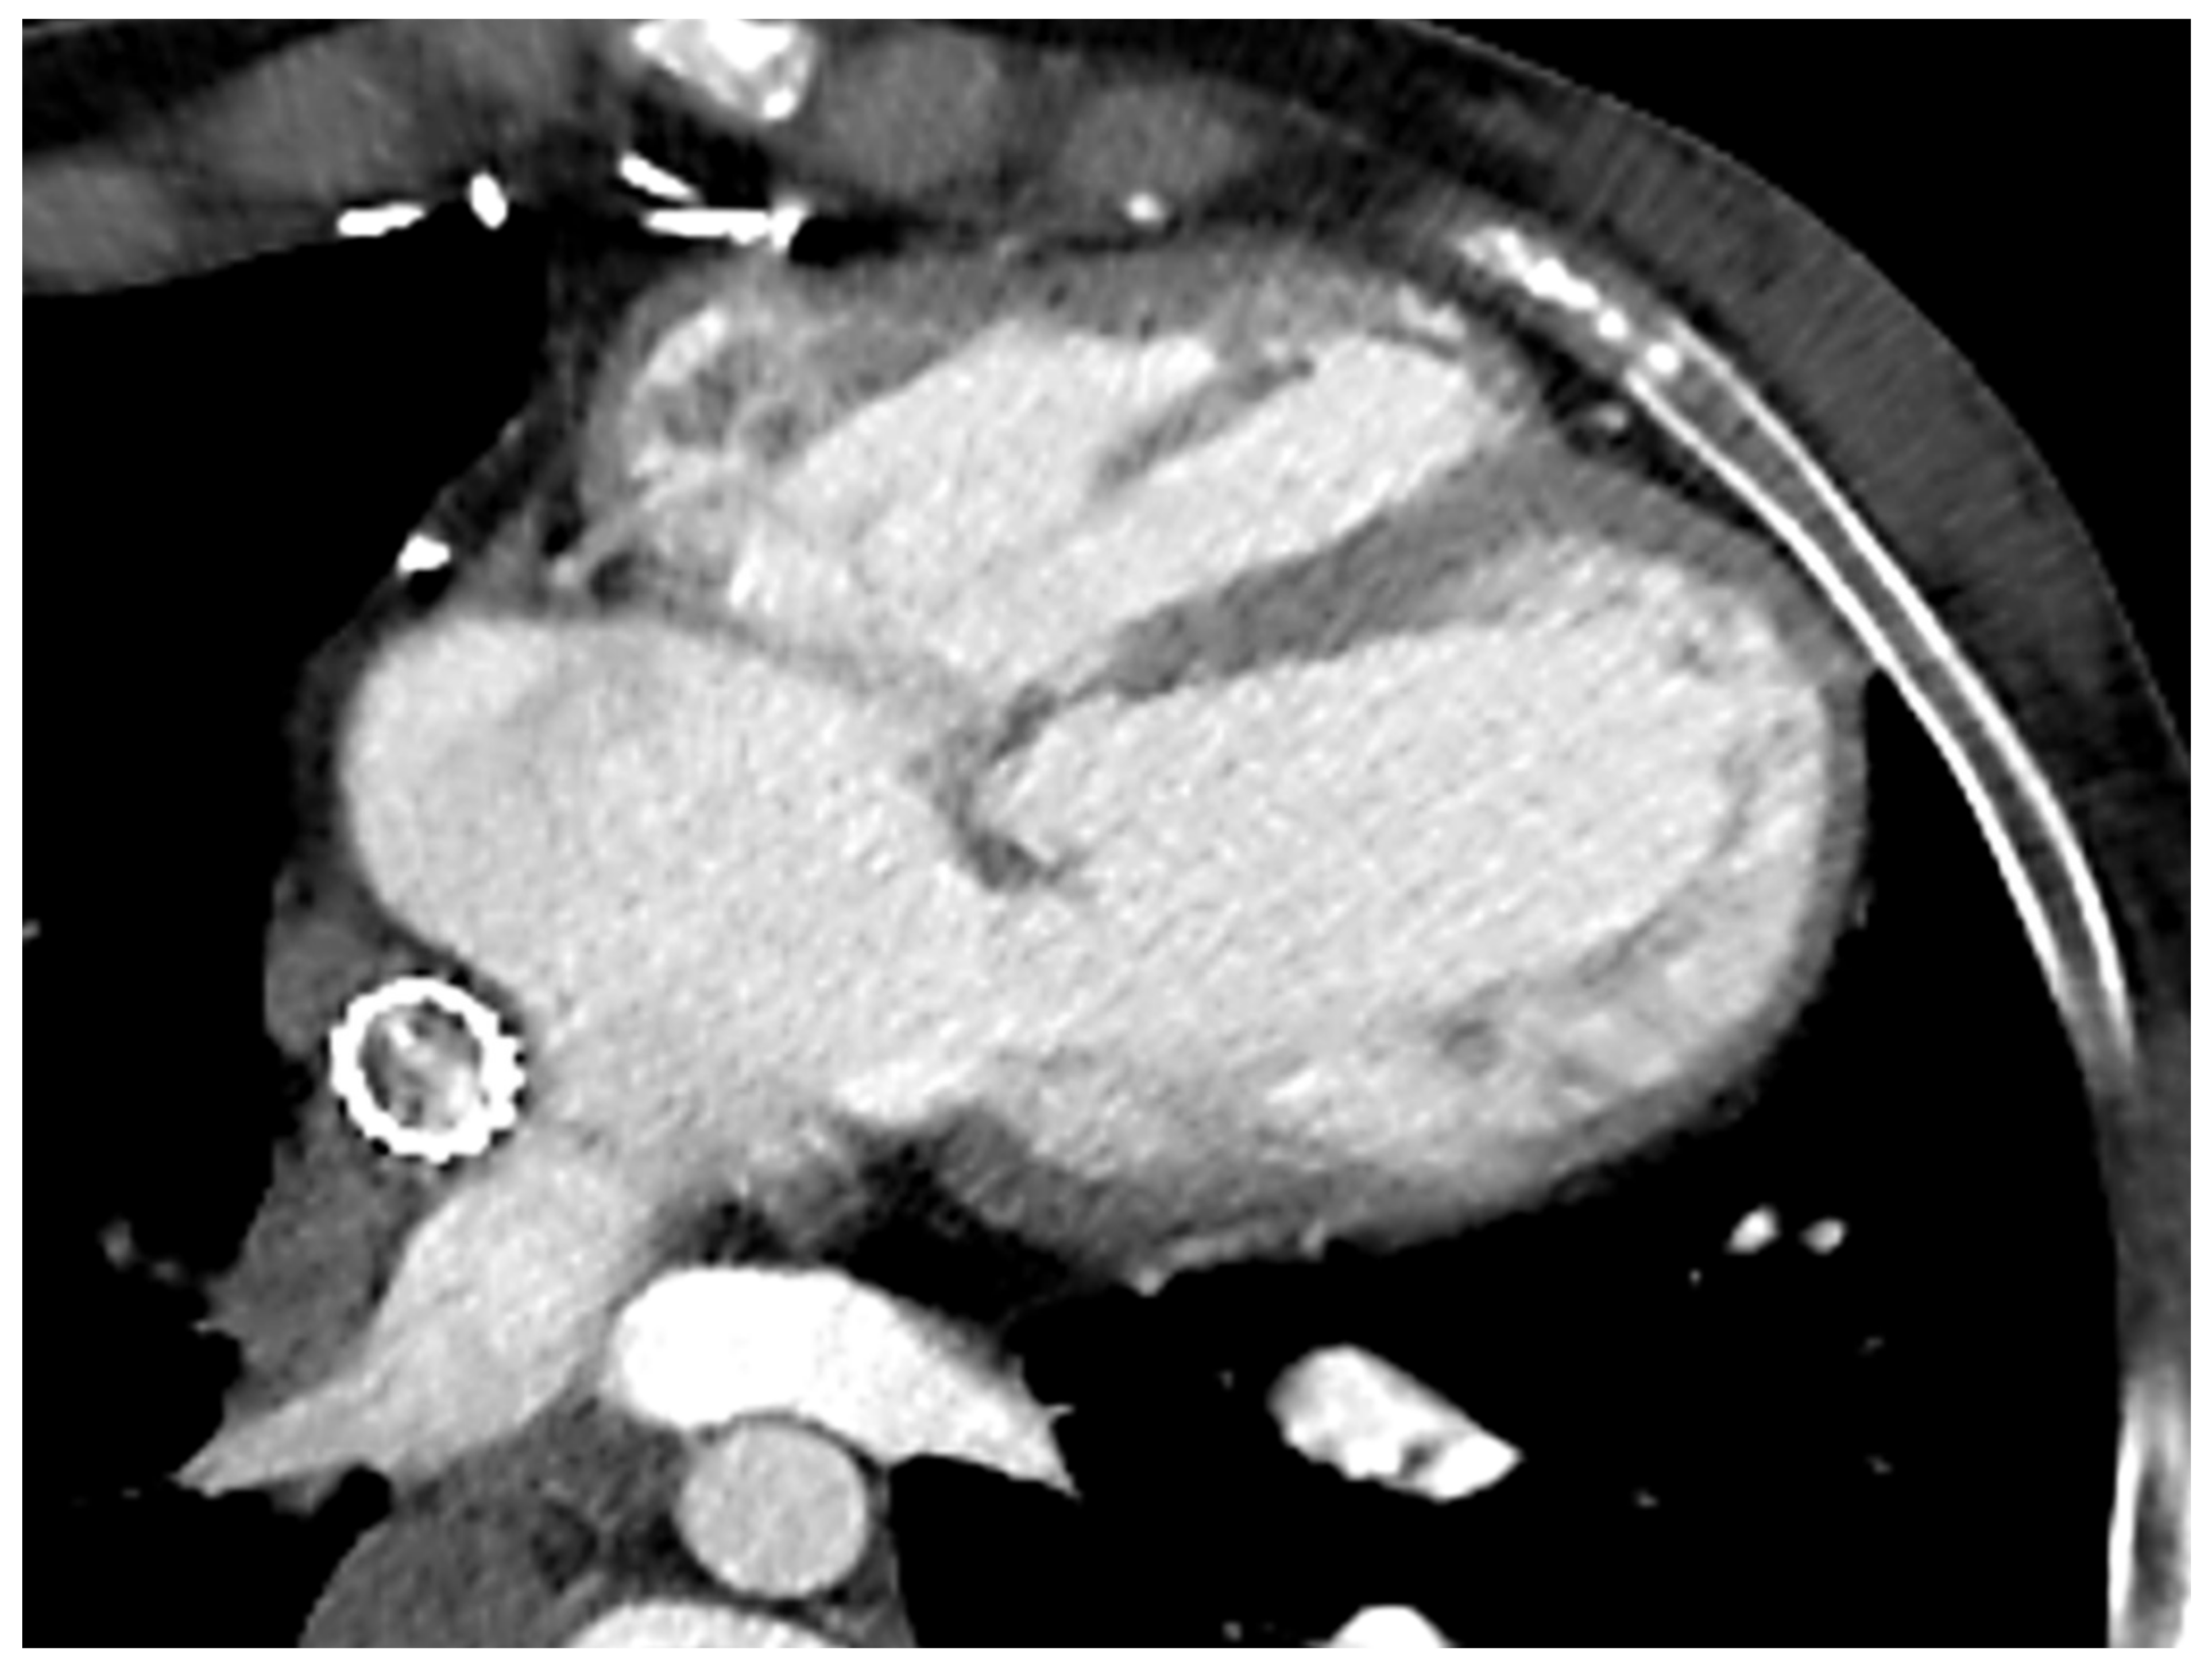

Moreover, 3D whole-heart SSFP allows a comprehensive and detailed evaluation of intracardiac and extra-cardiac morphology; it permits the visualisation of the arterial and venous systems together with their collaterals and the measurements of their vessels’ size. In adolescents and adults, it is acquired during mid-diastole when the heart is still, but, in children, due to the high heart rate, it may be necessary to plan it at the end-systolic phase of the cycle Figure 3.

Figure 3. (A) bSSFP image of Fontan conduit; (B) modified bSSFP four-chamber view with small VSD in the IVS; (C) 3D reconstruction of Fontan circuit.